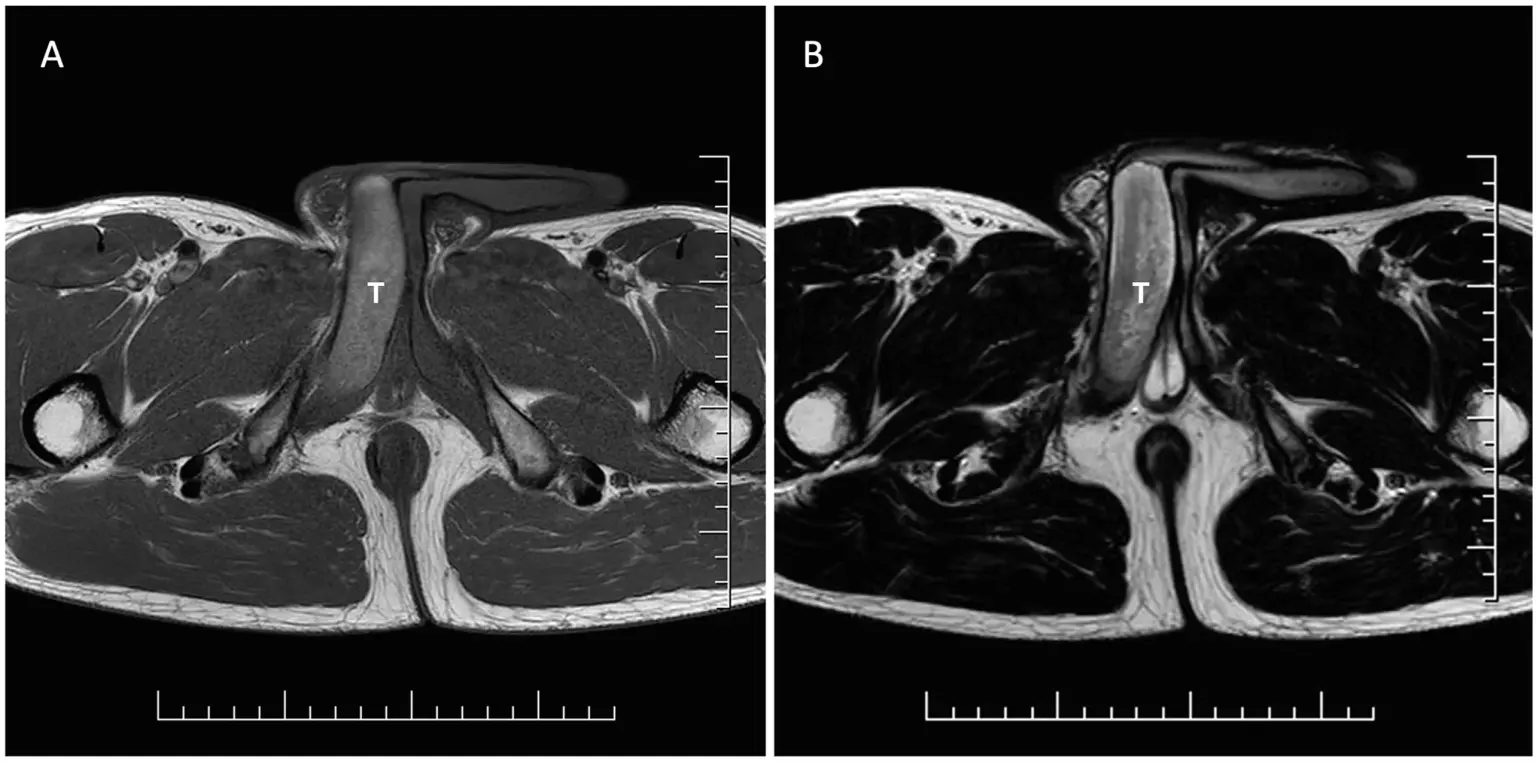

Μια μαγνητική τομογραφία από το νοσοκομείο Bory στη Μπρατισλάβα έδειξε ότι είχε θρόμβο αίματος πλάτους 18 χιλιοστών στα σηραγγώδη σώματα, που μπορούν να παρομοιαστούν με κυλίνδρους που γεμίζουν με αίμα και προκαλούν τη στύση